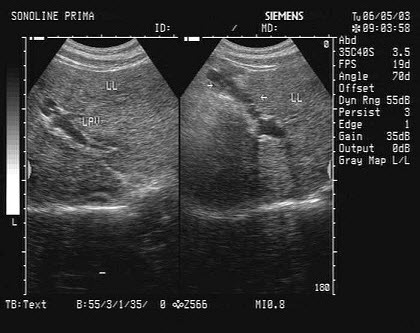

3、单项选择题

男,18岁,外伤1小时就诊。结合超声声像图,诊断为()

A.脾外伤血肿

B.脾淋巴管瘤

C.膈下积液

D.脾皮样囊肿

E.脾血管瘤